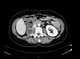

Pseudoenlargement of psoas muscle

Enlarged iliopsoas muscle